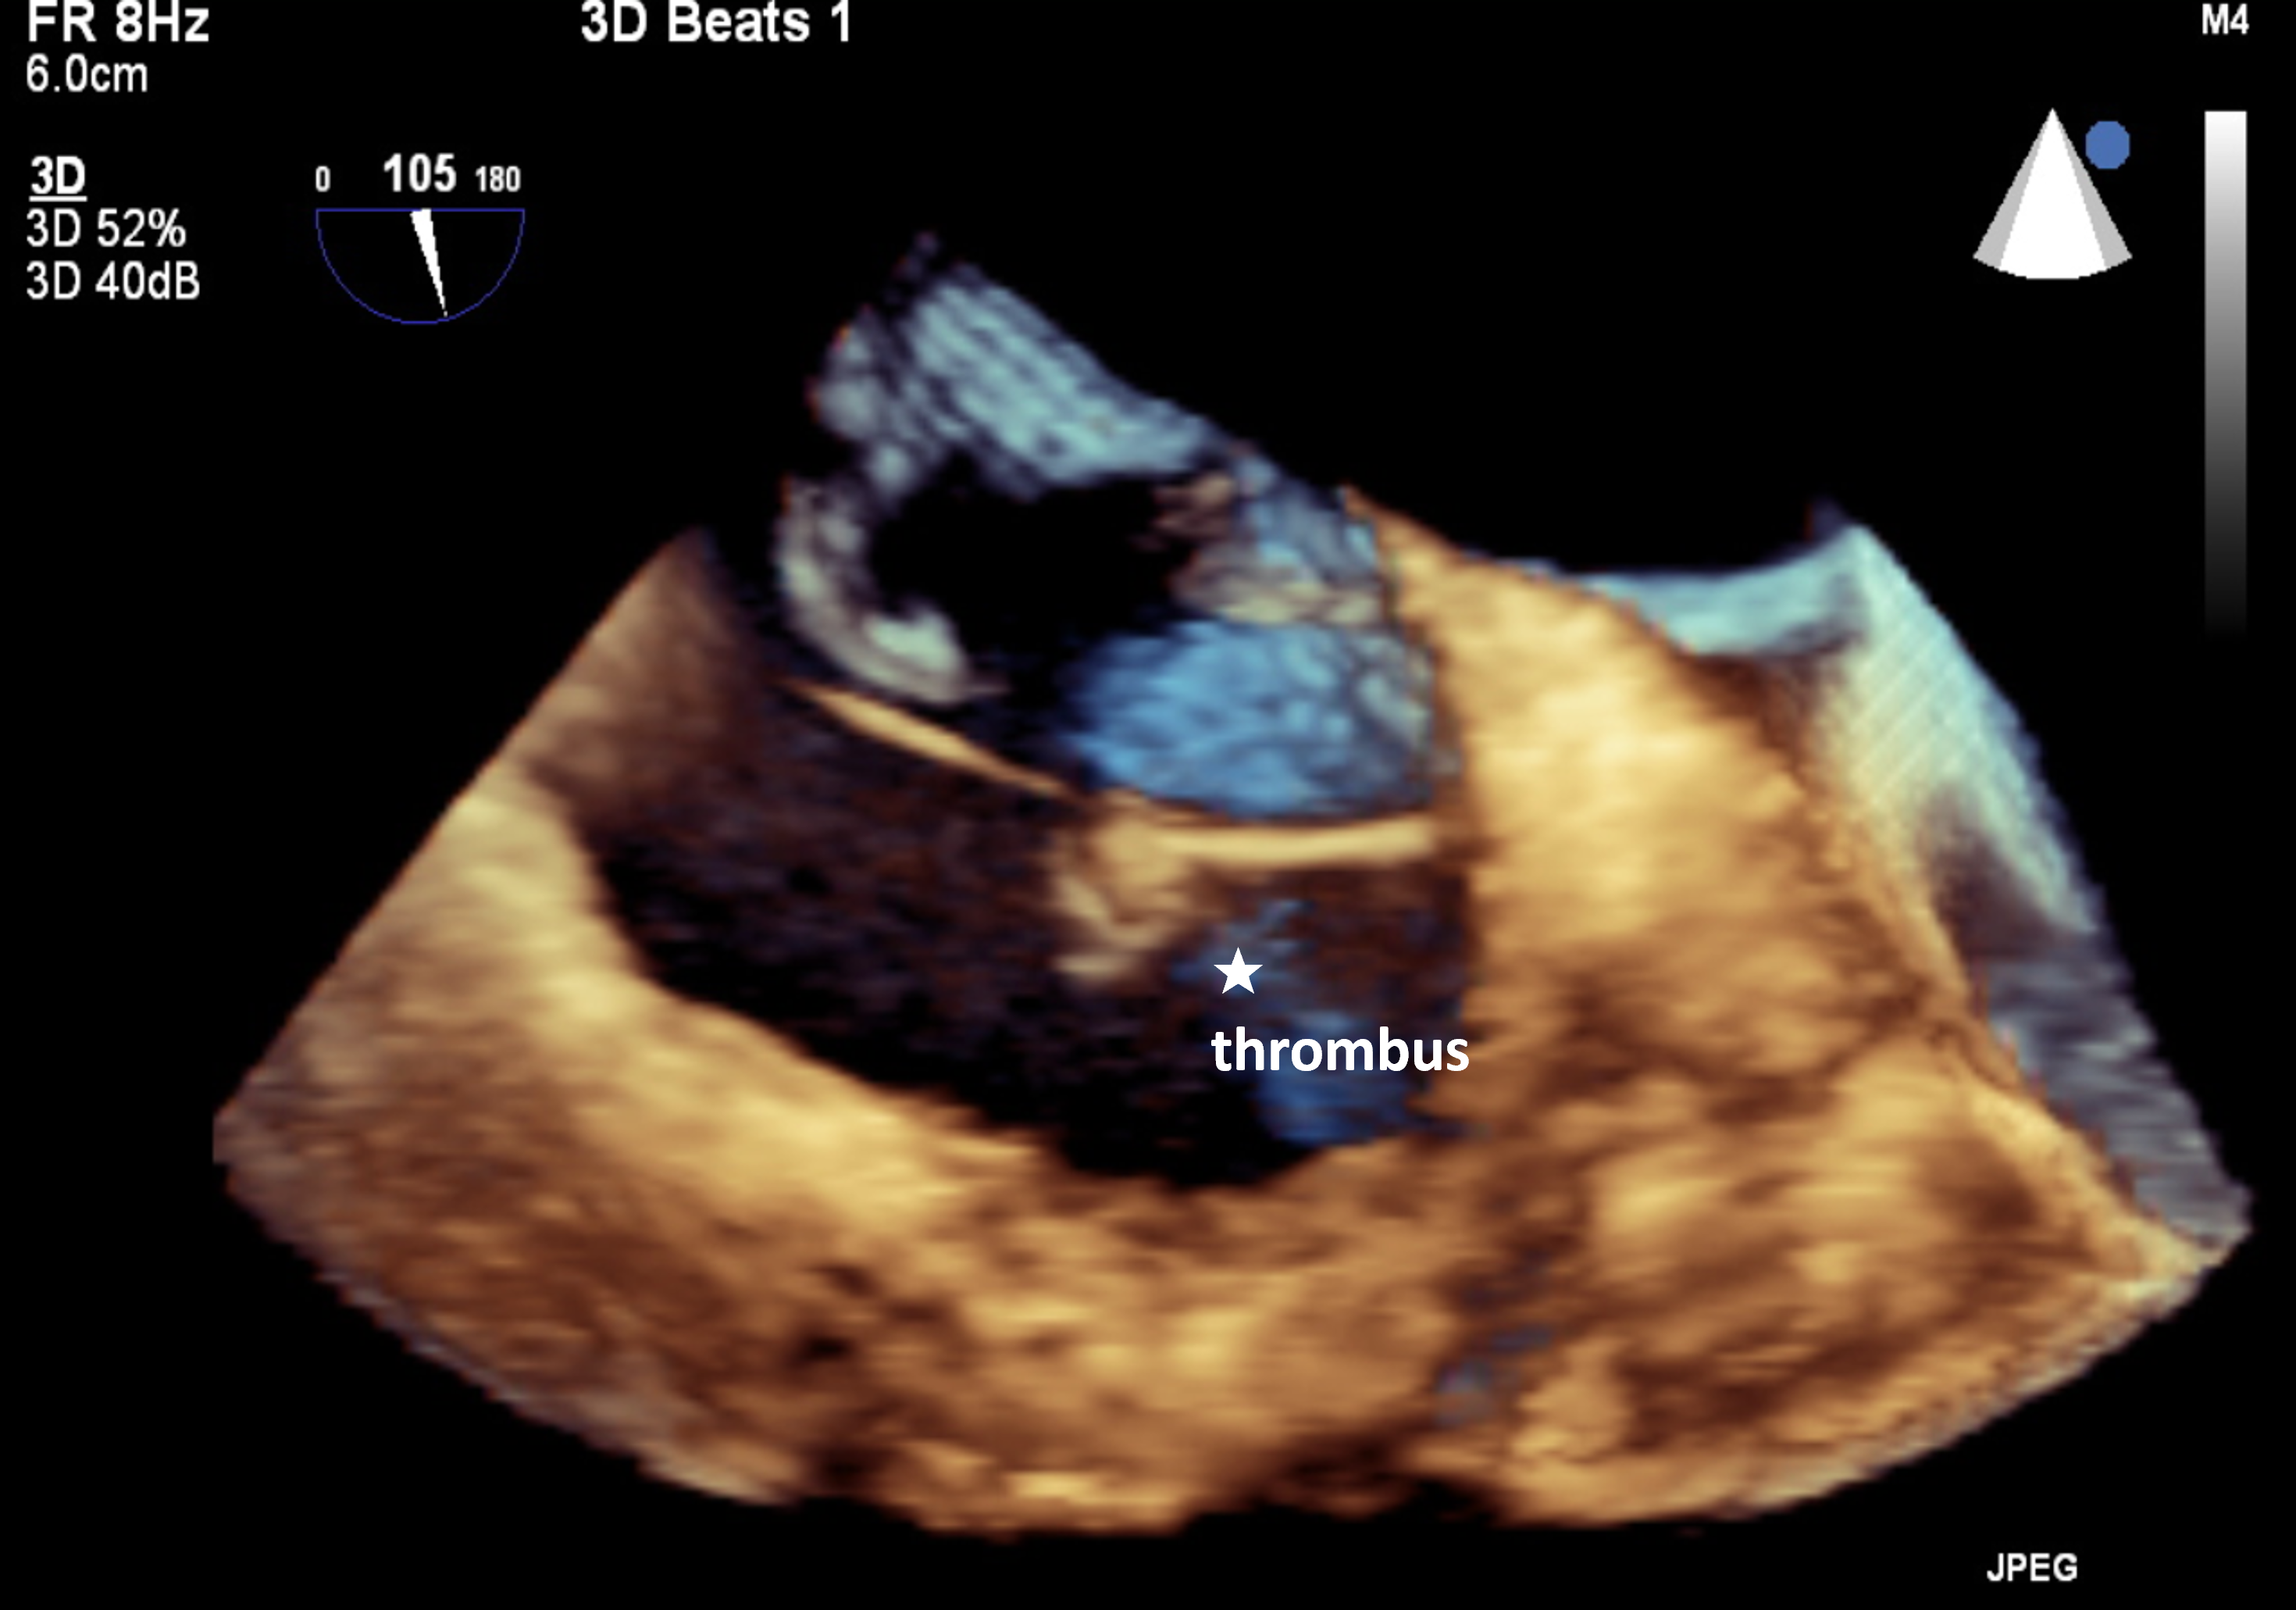

At the beginning of the procedure, the patient received unfractionated heparin and achieved an appropriate activated clotting time of 220 seconds. During right heart catheterization, the patient developed acute onset atrial fibrillation. As the catheter was advanced through the ASD, thrombotic material was suspected on 2-dimensional transesophageal echocardiography (TEE). Three-dimensional TEE confirmed the presence of a large thrombus attached to the Eustachian valve (Figure, Videos 1-3).